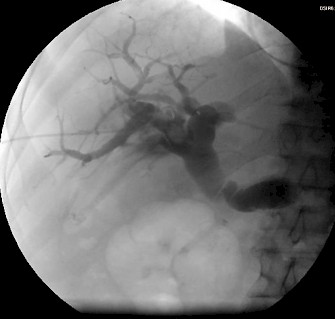

Die perkutane transhepatische Cholangiographie (PTC) ist ein interventionelles Verfahren, bei dem mit Hilfe einer dünnen Hohlnadel unter Durchleuchtungskontrolle perkutan (durch die Haut) durch Punktion der Leber Röntgenkontrastmittel in das Gallenwegsystem eingebracht wird.

Zusätzlich ist es möglich über diesen Zugang eine Ableitung der Gallenflüssigkeit nach außen über eine Drainage herzustellen (perkutane transhepatische Cholangiodrainage, PTCD oder auch perkutane transhepatische Drainage, PTD), um einen Rückstau in den Gallenwegen zu beseitigen.

Bei der PTC handelt es sich um eine direkte Cholangiographie, bei der eine Darstellung der Gallenwege inner- und außerhalb der Leber möglich ist. Wichtig zu wissen ist dabei, dass sich die beiden (den größeren rechten und den kleineren linken) Leberlappen drainierenden Hauptgallengänge in der sog. Hepatikusgabelung vereinigen und die Galle aus der Leber über den gemeinsamen Gallengang (den Ductus hepatocholedochus) ins Duodenum ableiten. Die Darstellung der Gallengänge in der PTC und ERCP stellt im Vergleich zur MRT/MRCP und dem CT weiterhin den Goldstandard dar.

Fallbeispiel:

Patient mit Pankreaskopf-Ca, Leber- und Lungenmetastasen und Tumorverschluß des Gallengangs: